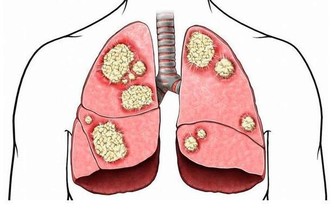

世界上沒有不衰老的血管,正常人的血管每年變窄1%-2%;有高血壓、高血黏度、糖尿病者,每年變窄3%-4%或以上。

當動脈血管堵塞75%以上,血流量過少時,胸悶、氣短、頭暈、頭痛等不適就會出現,更嚴重還會誘發腦卒中、心肌梗死等疾病。